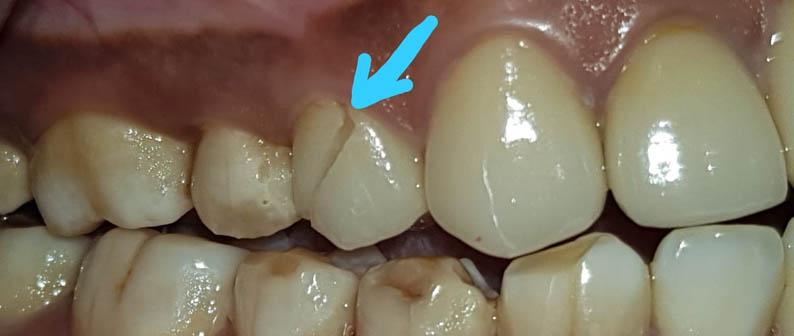

याशिवाय माणसाच्या उत्क्रांती मुळे कमी होणाऱ्या जबड्यांच्या आकारावर दातांची संख्या तेवढीच म्हणजे 32 राहिल्यामुळे सर्वात शेवटी उगवणाऱ्या अक्कलदाढा अडकल्यामुळे ,किंवा तिरक्या उगवल्यामुळे, बहुतांशी रुग्णांना शस्त्रक्रिया (ऑपरेशन) करून काढून टाकाव्या लागतात. अन्यथा या दाढांमुळे, पुढचे सर्व दात वाकडेतिकडे होण्याची किंवा पुढे येण्याची शक्यता असते.

याशिवाय आजकालची प्रमुख समस्या म्हणजे पुढे आलेले दात किंवा दात वाकडेतिकडे असणे, दातांमध्ये फटी असणे की ज्यामुळे तुमचा चेहरा, तुमचं हसणं विद्रूप तर दिसतंच पण त्यामुळे खाताना, गिळताना, बोलतानाही त्रास होतो तो वेगळाच ... यावर दंततव्यगोपचार (ऑर्थोडोंटिक) हे प्रभावी माध्यम (उपचार) आहे. दाताना क्लिप्स लावून असे वाकडे तिकडे दात सरळ रेषेत येतात, पुढे आलेले दात मागे नेता येतात, दातातील फटीही बंद करता येतात. याशिवाय, जास्त वाढलेला जबड्यांची दुरुस्तीही योग्य तऱ्हेने करता येते. वाढीचे वय संपून गेल्यानंतरही, प्रौढांनाही कमी किंवा जास्त वाढलेल्या जबड्यावर शस्त्रक्रिया करून सुंदर चेहरा मिळविता येतो. उपचार चालू असताना अवघडल्यासारखे (awkward) वाटू नये म्हणून विशेषतः प्रौढांना, दातांच्या रंगाच्या, कमीत कमी दिसणाऱ्या क्लिप्स ही उपलब्ध आहेत. याच सोबत अलायनर्स(aligners)म्हणजे अजिबात न दिसणाऱ्या क्लिप्स सुद्धा उपलब्ध आहेत.